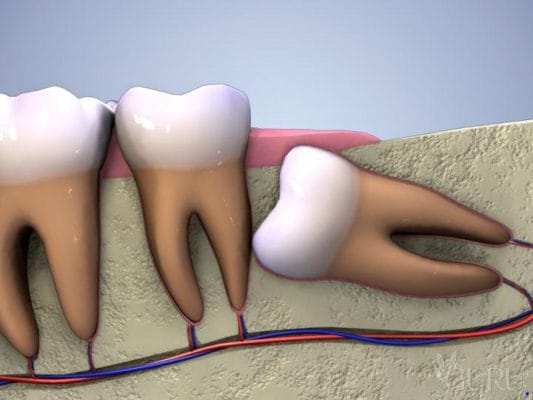

- Phân biệt theo vị trí: Răng khôn hàm dưới thường phức tạp hơn do gần các dây thần kinh quan trọng, do đó chi phí thường cao hơn so với răng khôn hàm trên.

3.2. Vị trí Răng Khôn (Hàm Trên – Hàm Dưới)

Răng khôn hàm dưới thường có chi phí cao hơn răng khôn hàm trên. Lý do là hàm dưới có cấu trúc xương dày hơn, đồng thời vị trí nhổ thường gần dây thần kinh hàm dưới, yêu cầu độ chính xác và cẩn trọng cao hơn trong quá trình phẫu thuật.

4.2. Giá Nhổ Răng Khôn Mọc Lệch

Độ khó tăng lên do răng chỉ mọc một phần và bị nghiêng, thường đâm vào răng số 7. Bác sĩ cần phải rạch lợi và đôi khi phải chia nhỏ thân răng trước khi lấy ra, làm tăng thời gian phẫu thuật và chi phí cao hơn so với răng mọc thẳng.

4.3. Giá Nhổ Răng Khôn Mọc Ngầm, Phẫu thuật

Đây là nhóm chi phí cao nhất. Trường hợp này yêu cầu tiểu phẫu phức tạp, cần gây tê chuyên sâu, đôi khi phải khoan xương và cắt thân răng thành nhiều phần để lấy ra, đảm bảo không làm tổn thương cấu trúc xương hàm. Chi phí này bao gồm cả phẫu thuật, gây tê, và chăm sóc hậu phẫu kỹ lưỡng.